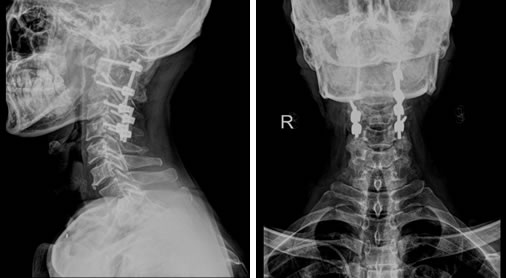

5月8日,决定治疗成败的关键一天到来了。因手术是经后路进行,需要神经外科的特殊头架固定,治疗团队特邀本部神经外科江常震副主任医师指导头架的使用及固定。手术由骨科陈飞博士主刀,历时约5小时,出血仅150ml,麻醉清醒后,病人四肢感觉、运动功能正常,生命体征平稳,表明未损伤颈髓和椎动脉。术后,患者颈部疼痛明显缓解,术后一天就拔除了气管插管,回到普通病房,并可以自行坐起。